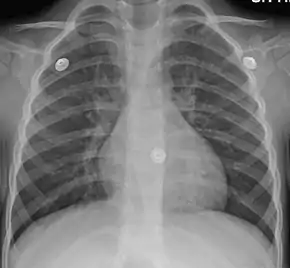

| Figure A shows the location of the lungs and bronchial tubes. Figure B is an enlarged view of a normal bronchial tube. Figure C is an enlarged view of a bronchial tube with bronchitis. | |